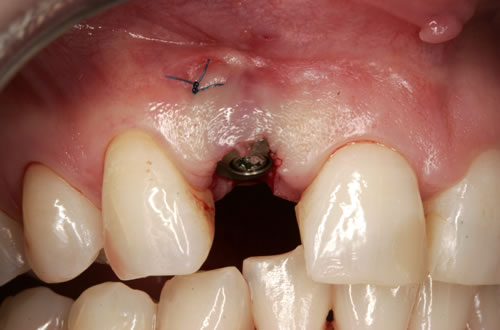

In einigen Fällen werden die Implantate am gleichen Tag wie die Entfernung der Zähne eingesetzt. Man spricht dann von einer Sofortimplantation (Abb. 2.3, 2.4). Wenn die Eingliederung des Zahnersatzes als Stegprothese oder als provisorische Krone innerhalb der ersten 24 Stunden direkt auf den frisch gesetzten Implantaten befestigt wird, dann wird auch von einer Sofortbelastung gesprochen. Für eine Sofortimplantation und Sofortbelastung müssen wichtige Kriterien erfüllt werden. Hierzu zählen ein ausreichendes Knochenangebot in Höhe und Breite, damit ein möglichst groß dimensioniertes Implantat gesetzt werden kann, entzündungsfreie Verhältnisse und eine gute Mitarbeit der Patienten. Wichtig ist auch, dass die Patienten ihre „neuen Zähne“ zunächst nur sehr vorsichtig benutzen, denn bei der Stabilität der neugesetzten Implantate handelt es sich zunächst um eine mechanische Stabilität, die in eine biologische Stabilität umgewandelt wird. Vergleichbar ist ein gebrochener Arm, mit dem man ja auch nicht nach einer Eingipsung sofort Tennis spielen gehen sollte. Aber nach der Knochenbruchheilung wird das Tennis spielen genauso gut funktionieren wie vor der Verletzung. In ähnlicher Weise funktioniert das Einwachsen der Implantate.

Abb. 2.3: Wurzelrest im Kiefer.

Abb. 2.4: Sofortimplantation nach Entfernung des reizlosen Wurzelrestes mit Abdeckschraube verschlossen.